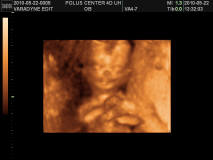

Szóval iszonyu alaposan átnézte mindenét és folyamatosan magyarázta mit látunk(pedig minden teljesen egyértelmű volt) és dicsérte milyen édes, formás tökéletes. A mérteét tartja továbbra is 14 hetes pont :-) És kiderült hogy kisfiú, egyértemműen látszódott. teszek fel képet is. Szopta az úját, és mozgott végig. És nagyon szófogadó, mert többször is hátat forditott, de amikor kértem hogy forduljon visssza, vagy emelje fel a karját és integessen, megtette :-) Szóval hallgat rám, remélem így is marad egy 20 évig :-D ja és folyamatason mosolygott....

Kép bizonyíték hogy fiú Kép mosolyog